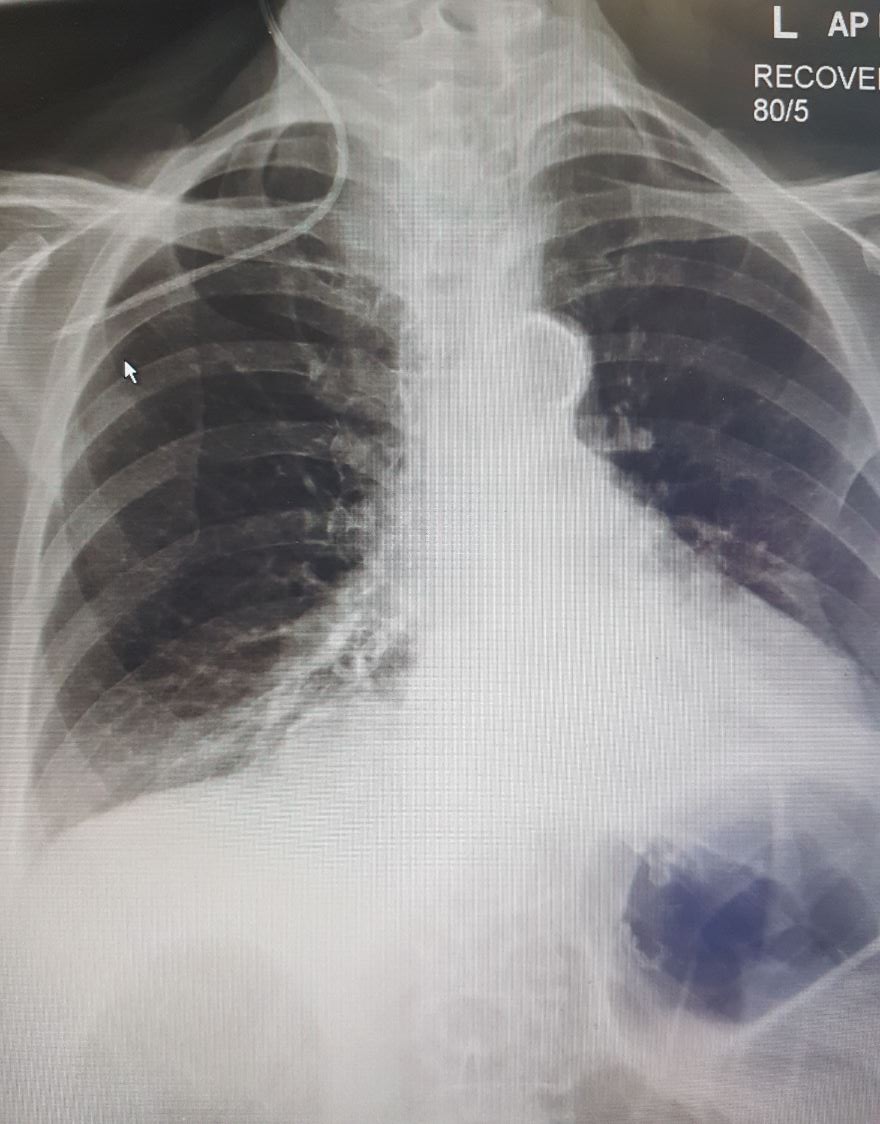

- Management of pneumothorax

- Of 23 patients with confirmed pneumothorax, (18 were right side and 5 left side)

- 15 successfully treated with conservative management.

- 8 (0.12% of 6875) required a chest drain to be inserted

- 5 immediately after the pneumothorax identified

- 2 on post-procedural day 1

- 1 on post-procedural day 2